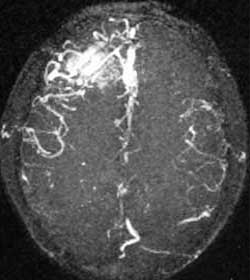

二、脑动静脉畸形(AVM)

---- Spetzler对AVM的分级方法已越来越多地被人们接纳和采用。脑AVM最危险的症状之一是出血。AVM每年的出血率为3%~4%,第一年内再出血约6%。每次出血的致残率为30%,病死率为12.5%,而积极治疗的总残废率加病死率在10%以下。

血管内栓塞对于单支或少数供血动脉的AVM,特别是新近出血的病例,可以达到微侵袭、痛苦小、疗效迅速的目的。

近来改变栓塞方式,将导管直接放置 畸形血管团内,注射NBCA胶,可使畸形团的解剖 治愈率提高至27%。再加上更细、超滑的微导管问世,栓塞的并发症更为降低。针对大型、功能区 的AVM栓 塞可缩小其体积,改善血液动力学分布,以利于显微外科技术切除或放射外科治疗,是后二者的重要辅助手段。